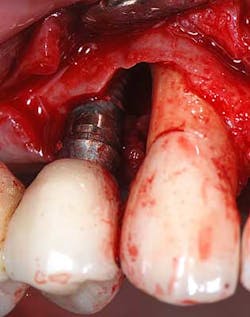

Intraoperative photo

- Intrasulcular incisions

- A full thickness flap was reflected

- Thorough debrided and degranulation with hand instrumentation and a Cavitron

- Cortical-cancellous allograft was mixed with enamel matrix derivative for 15 minutes

- A tetracycline slurry was used for chemical conditioning of the tooth and the implant surface for approximately two minutes, and then thoroughly irrigated with saline rinses

- EDTA 24% was placed on both implant and tooth and allowed to sit for four minutes, rinsed, and dried with nonwoven gauze

- Enamel matrix derivative was added to the base of the alveolar defect on tooth No.6 and implant No. 5

- A combination of allograft and enamel matrix derivative was placed into both defects

- 4-0 vicryl vertical mattress sutures were used to coronally advance the tissue along with simple interrupted sutures